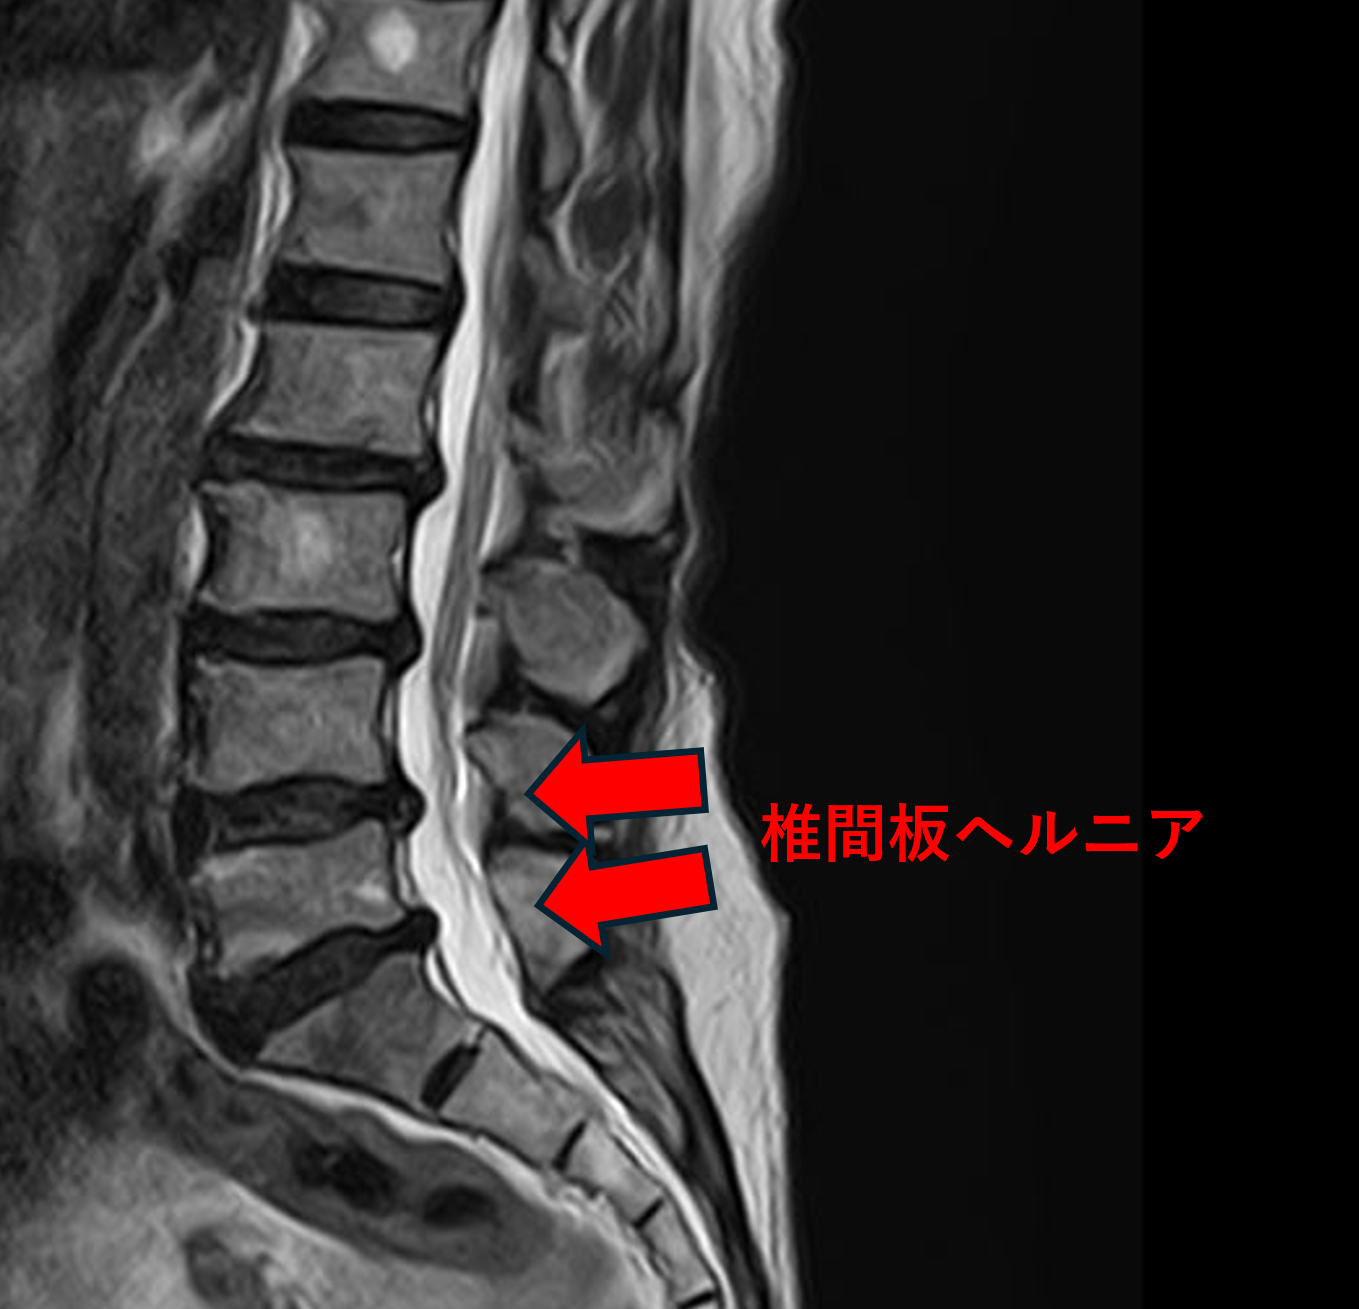

画像及び所見について

- L2/3、4/5 – 椎間板変性、膨隆

- L3/4、5/s – 椎間板変性、椎間板ヘルニア

以上のことが画像上認められました。

L2/3、3/4、4/5、5/sの椎間板所見による脊柱管の圧排が、症状の原因の可能性が高い。